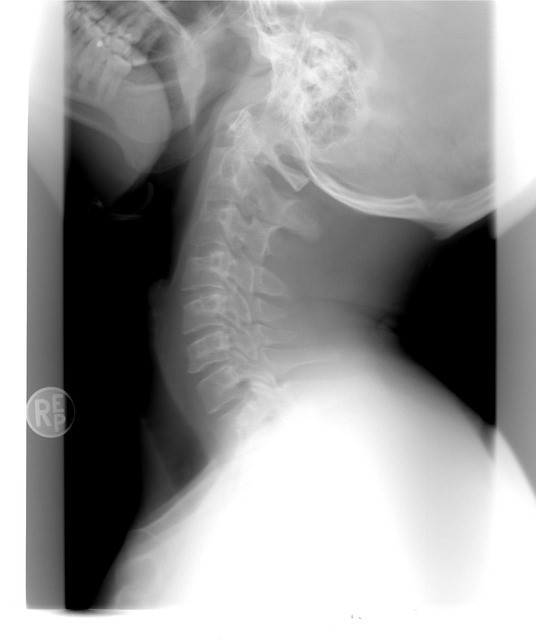

경추디스크란 목 부위의 척추뼈 사이에 있는 디스크, 즉 추간판이 파열되거나 탈출하여 인접한 신경을 압박하는 상태를 말합니다. 의학적으로는 ‘경추 추간판 탈출증’이라고 부르며, 척추의 C5~C7 사이에서 자주 발생합니다. 디스크는 젤리처럼 부드러운 수핵과 이를 감싸는 섬유륜으로 구성되며, 외부 압력이 지속되면 섬유륜이 손상되어 수핵이 탈출하게 됩니다. 탈출한 수핵은 신경을 자극하여 통증과 감각 이상, 운동 기능 저하 등을 유발합니다.

경추디스크는 단순한 근육통이나 뻐근함으로 오인되기 쉬우나, 증상이 일주일 이상 지속되거나 저림이 동반될 경우 반드시 영상진단(MRI, CT)을 통한 정밀 검사를 받는 것이 중요합니다. 초기에는 휴식과 물리치료로도 호전될 수 있지만, 방치 시 만성화되거나 신경 손상으로 발전할 위험이 있으므로 조기 진단과 대응이 필요합니다.